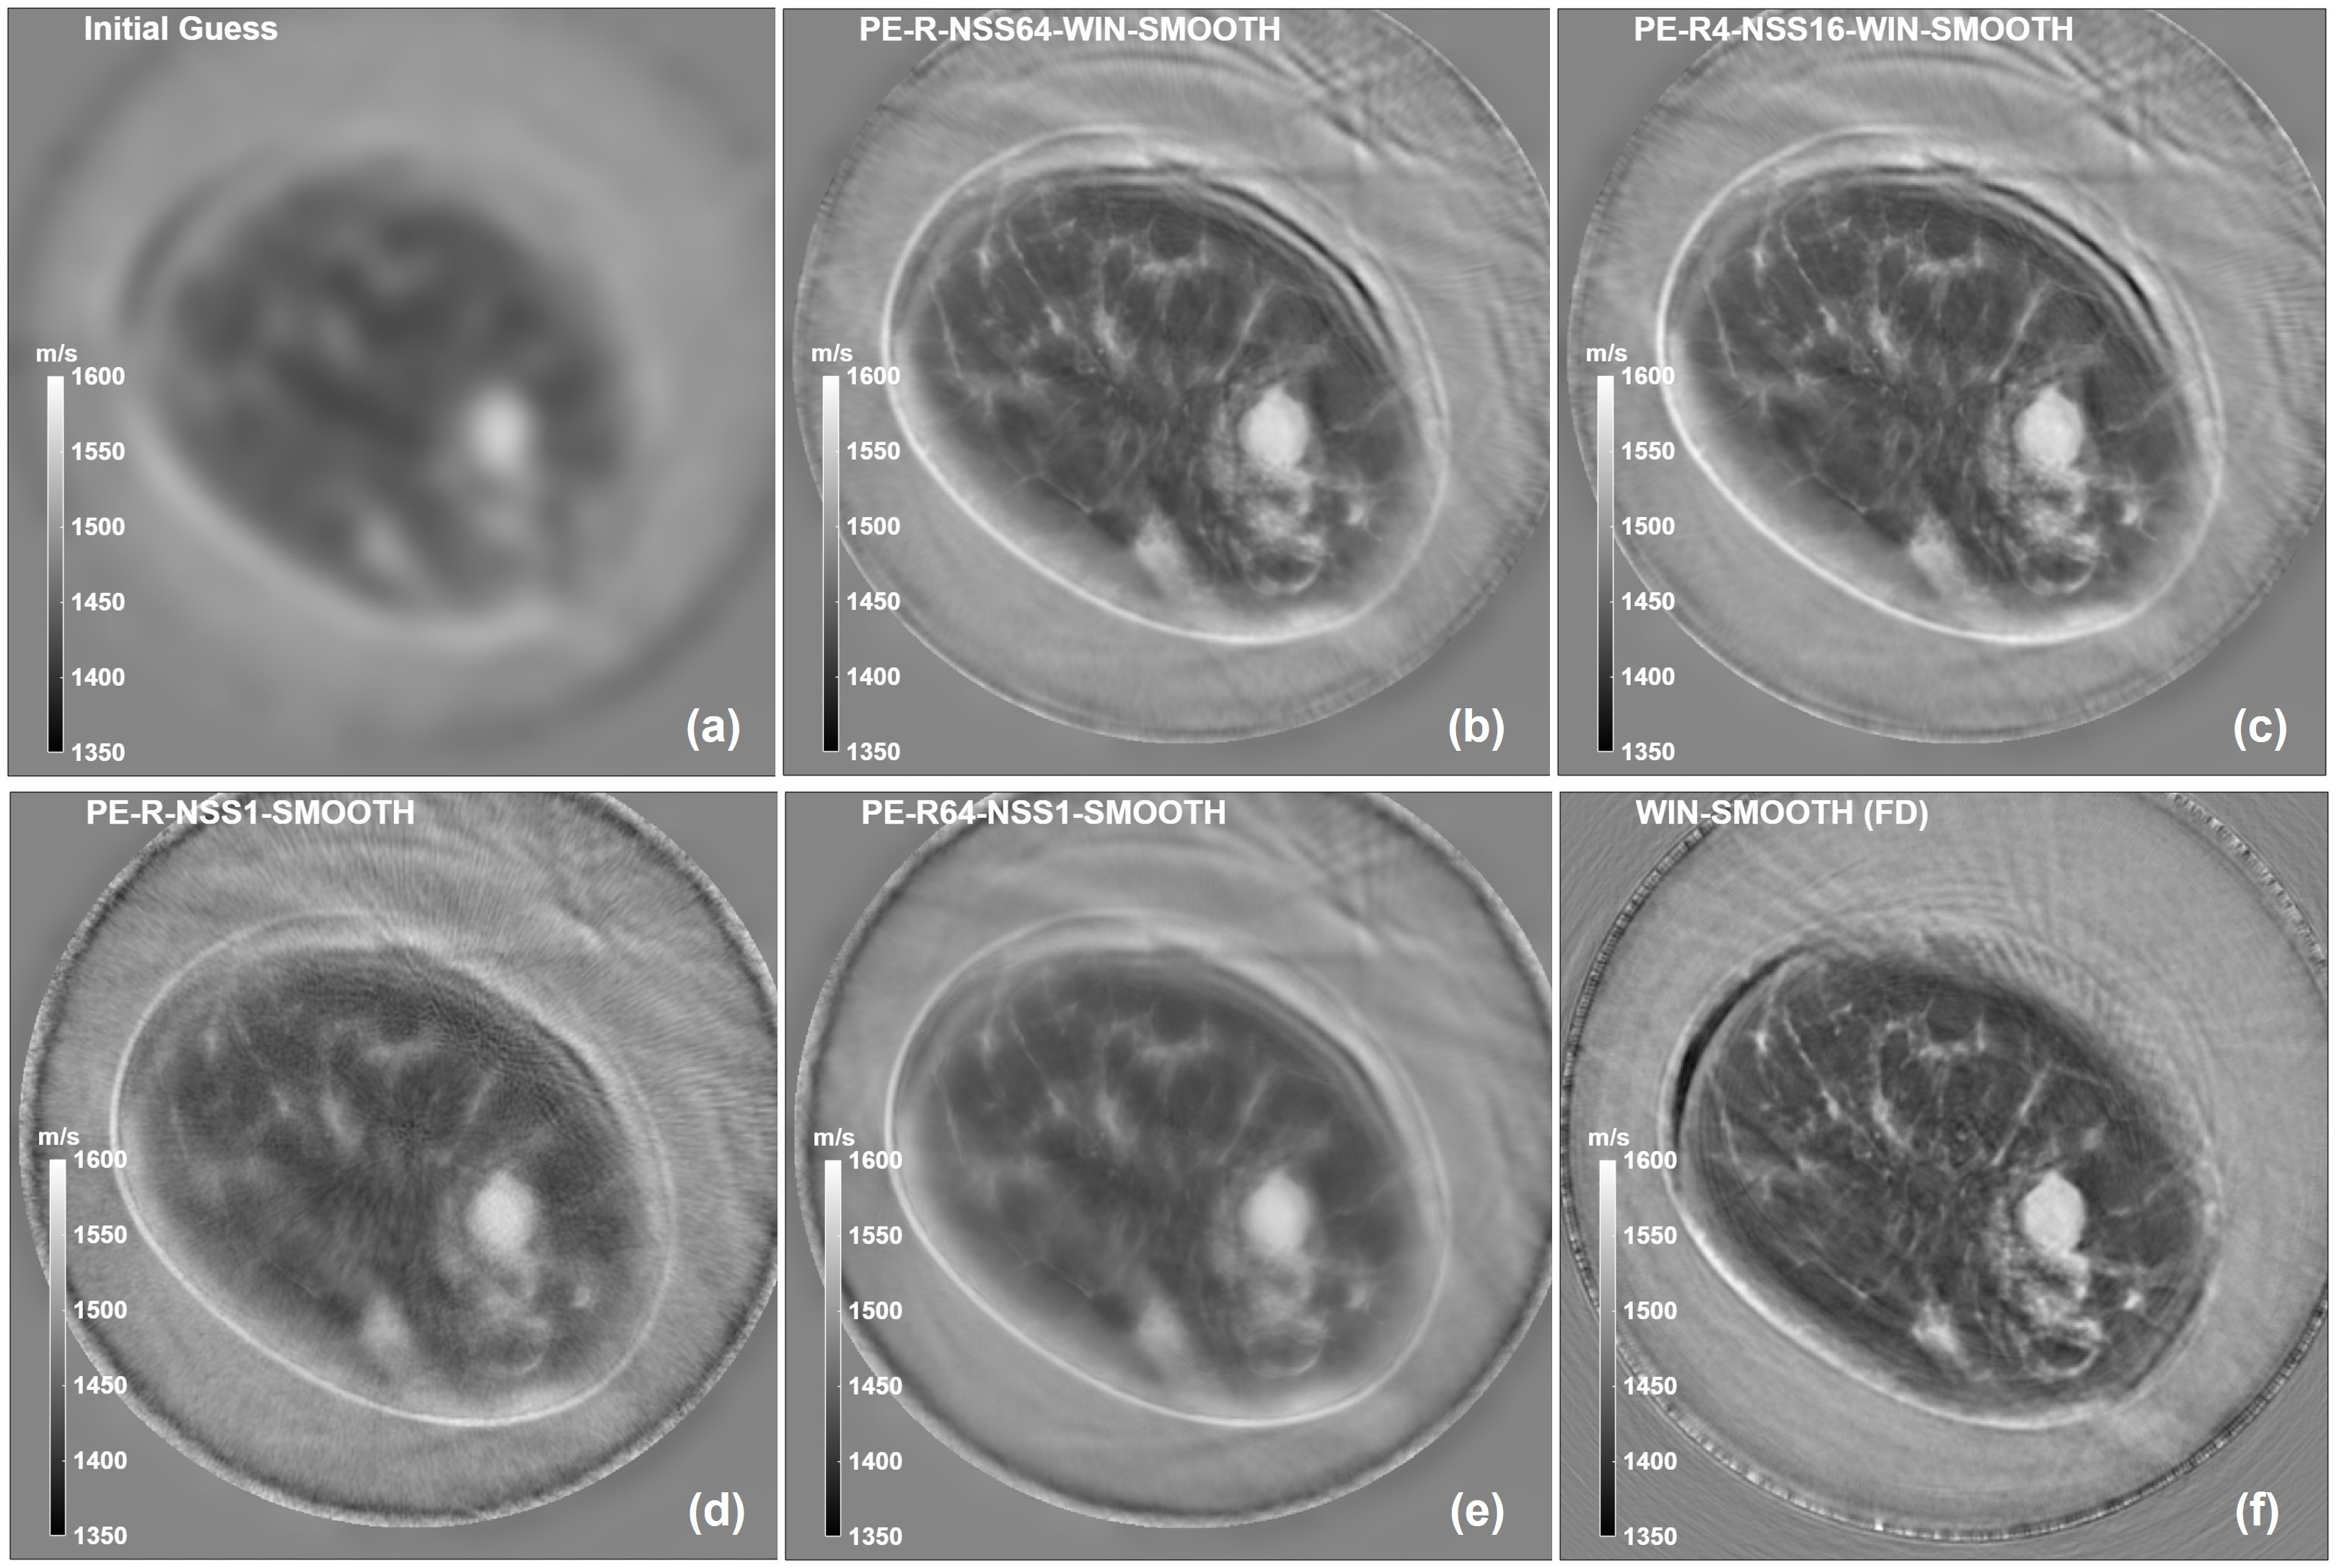

Figure 2: Stochastic reconstruction with super-shots and stochastic ensembles. Reconstructed images and cost functions for experimental data (Malignancy). (a) Initial guess for TD-reconstructions in (b)-(e). (b) TD stochastic image reconstruction with multiple super-shots (Nss=64,NPE=1N_{{}_{ss}}=64,N_{{}_{PE}}=1). (c) TD stochastic image reconstruction with multiple super-shots (Nss=16N_{{}_{ss}}=16) and multiple stochastic ensembles (NPE=4N_{{}_{PE}}=4). (d) TD stochastic image reconstruction with one super-shot (Nss=1,NPE=1N_{{}_{ss}}=1,N_{{}_{PE}}=1). (e) TD stochastic image reconstruction with one super-shot (Nss=1N_{{}_{ss}}=1) and multiple stochastic ensembles (NPE=64N_{{}_{PE}}=64). (f) FD deterministic image reconstruction from 300 kHz to 1 MHz from a flat initial guess. (g) TD stochastic image reconstruction with multiple super-shots (Nss=64,NPE=1N_{{}_{ss}}=64,N_{{}_{PE}}=1) from a flat initial guess, showing cycle-skipping artifacts. TD inversions are run for 40 iterations; FD inversion is run for 10 iterations per frequency (cost function not shown). For all reconstructions, the same Gaussian smoothing filter has been applied on the final gradient before updating the speed of sound.

We now present the results of the reconstruction algorithm on two experimental data-setsAli et al. (2024), a patient with a malignant mass and a patient with a cyst. The raw data show spectral contents that extend roughly from 300 kHz to 3 MHz, Fig. 1. This is too wide for a TD reconstruction, hence the first step is to apply a band pass filter around 1 MHz. The reconstruction algorithm requires an initial estimate for the source term, siTx(𝒕)s_{i_{{}_{Tx}}}(\bm{t}). This can be extracted from raw data, Fig. 1(a) and (b); the same band-pass filter is then applied and a time-shifted, filtered pulse is finally obtained, Fig. 1(c) and (g). The latter is replicated across all the individual elements making the super-shot. The same source term is then updated at each iteration, as described in equations (7)- (14) above; in particular, the re-scaling factor is evaluated at all the frequency bins ωl\omega_{{}_{l}} in the 500 kHz - 1 MHz bandwidth, Fig. 1(d) and (h), as these have enough SNR and are not too close to the filter cut-off frequencies. The filtering operation results into Nt=1408N_{{}_{t}}=1408 time samples and a time step of dt=0.125μdt=0.125\,\mus (8 MHz). The reconstruction grid has a size of Nx×NyN_{{}_{x}}\times N_{{}_{y}} (Nx=Ny=875)(N_{{}_{x}}=N_{{}_{y}}=875) and a pixel size of dx=0.32dx=0.32 mm. The reconstruction algorithm has been implemented in MATLAB. In particular, the discretized wave equations, (5) and (16), have been solved with the popular k-Wave toolbox on the GPU (NVIDIA RTX A4000 16 GB); the rest of the algorithm runs on the CPU in single precision. The forward and adjoint wave-fields, 𝒑\bm{p} and 𝒒\bm{q} respectively, are natively vectors of size Nx×Ny×NtN_{{}_{x}}\times N_{{}_{y}}\times N_{{}_{t}}; as suggested in Wang et al. (2015), to reduce memory requirements due to the temporal dimension of these two vectors, both are stored only on a partial FOV (field of view), the latter essentially coinciding with the region bounded by the ring-array. This allows to evaluate the gradient, eq. (18), only on the chosen FOV and ultimately updating the speed of sound only on this FOV. To cope with experimental noise, a mild Gaussian smoothing filter (SMOOTH) has been applied on the final gradient before updating the speed of sound. When employing multiple super-shots, the receivers are selected by applying a rectangular window (WIN) across all possible array elements. A direct implementation of the reconstruction algorithm with multiple super-shots (Nss=64N_{{}_{ss}}=64) starting from a flat initial guess shows the known phenomenon of cycle-skipping, Fig. 2(g) and Fig. 3(g). Cycle-skipping is a form of non-linear aliasing that creates ghost structures vaguely resembling the true ones; this is due to the simultaneous inversion of a large frequency bandwidth, with the higher frequencies responsible for this behavior. To overcome this limitation, the inversion has to start from a non-trivial initial velocity model; the standard approach is to create a blurred image running a travel-time tomography reconstruction algorithm followed by standard FWI. Here we adopt a more practical approach where the initial guess is obtained by running a standard FD-FWI reconstruction algorithm up to 400 kHzAli et al. (2024); the resulting image is severely blurred before starting the TD-FWI reconstruction, Fig. 2(a) and Fig. 3(a). The reconstructed images obtained with a single super-shot (Nss=1,NTxss=NRxss=NTx=NRx=512,NPE=1N_{{}_{ss}}=1,N_{{}_{Tx}}^{{ss}}=N_{{}_{Rx}}^{{ss}}=N_{{}_{Tx}}=N_{{}_{Rx}}=512,N_{{}_{PE}}=1), Fig. 2(d) and Fig. 3(d), partially show the true distribution of the speed of sound of the breast slice. However, both show a peculiar image texture in the form of radial stripes (spokes), as already observed in Wang et al. (2015)-Matthews et al. (2017); this texture doesn’t disappear with increasing the number of iterations, it actually becomes more prominent. The main source of this texture is the residual cross-talk due to phase-encoding. To test this hypothesis, the reconstruction is run again with one super-shot (Nss=1,NTxss=NRxss=NTx=NRx=512N_{{}_{ss}}=1,N_{{}_{Tx}}^{{ss}}=N_{{}_{Rx}}^{{ss}}=N_{{}_{Tx}}=N_{{}_{Rx}}=512) and multiple stochastic ensembles (NPE=64N_{{}_{PE}}=64), Fig. 2(e) and Fig. 3(e): this is indeed effective in removing any image texture, as anticipated in the Conclusions section in Forte (2025). However, whereas the cyst dataset does show improved image quality, the malignancy one shows very little improvement. This is an indication that a single super-shot may not be reliable and that results may be data-dependent. We believe that the main reason behind this is that with a single super-shot it’s not possible to differentiate between reflection data and transmission data. The reconstruction is then run again, with multiple super-shots (Nss=64,NTxssi=86,NRxssi=384,NPE=1N_{{}_{ss}}=64,N_{{}_{Tx}}^{{ss_{{}_{i}}}}=86,N_{{}_{Rx}}^{{ss_{{}_{i}}}}=384,N_{{}_{PE}}=1), Fig. 2(b) and Fig. 3(b), and in combination with stochastic ensembles (Nss=16,NTxssi=86,NRxssi=384,NPE=4N_{{}_{ss}}=16,N_{{}_{Tx}}^{{ss_{{}_{i}}}}=86,N_{{}_{Rx}}^{{ss_{{}_{i}}}}=384,N_{{}_{PE}}=4), Fig. 2(c) and Fig. 3(c). For comparison, images reconstructed on the same computational grid with a deterministic inversion in the frequency domain are also shown (10 iterations per frequency, from 300 kHz to 1 MHz in steps of 100 kHz), Fig. 2(f) and Fig. 3(f). These results are in perfect agreement with what we have shown in Forte (2025) for the stochastic inversion in the frequency-domain. With all the caveats and the difficulties in assessing image quality, we feel that it is fair to claim that both TD and FD reconstructions display the same anatomy; in particular the relative contrast among the different tissues is preserved in all cases, although the TD reconstruction looks soft. There is, however, a significant difference in terms of computing time and resources. Whereas a FD deterministic inversion may take 60-90 minutes on a single GPUAli et al. (2024) and a FD stochastic one is much faster and provides comparable image quality Forte (2025), a TD stochastic reconstruction may take more than 24 hours with the same hardware architecture (by keeping fixed the product the product Nss×NPE=64N_{{}_{ss}}\times N_{{}_{PE}}=64), from a non-trivial initial guess; this explains why the TD stochastic reconstruction has been run only for 40 iterations. These considerations may rule out the feasibility of a stochastic inversion in time-domain in ring-array USCT, let alone any deterministic inversion in time-domain.